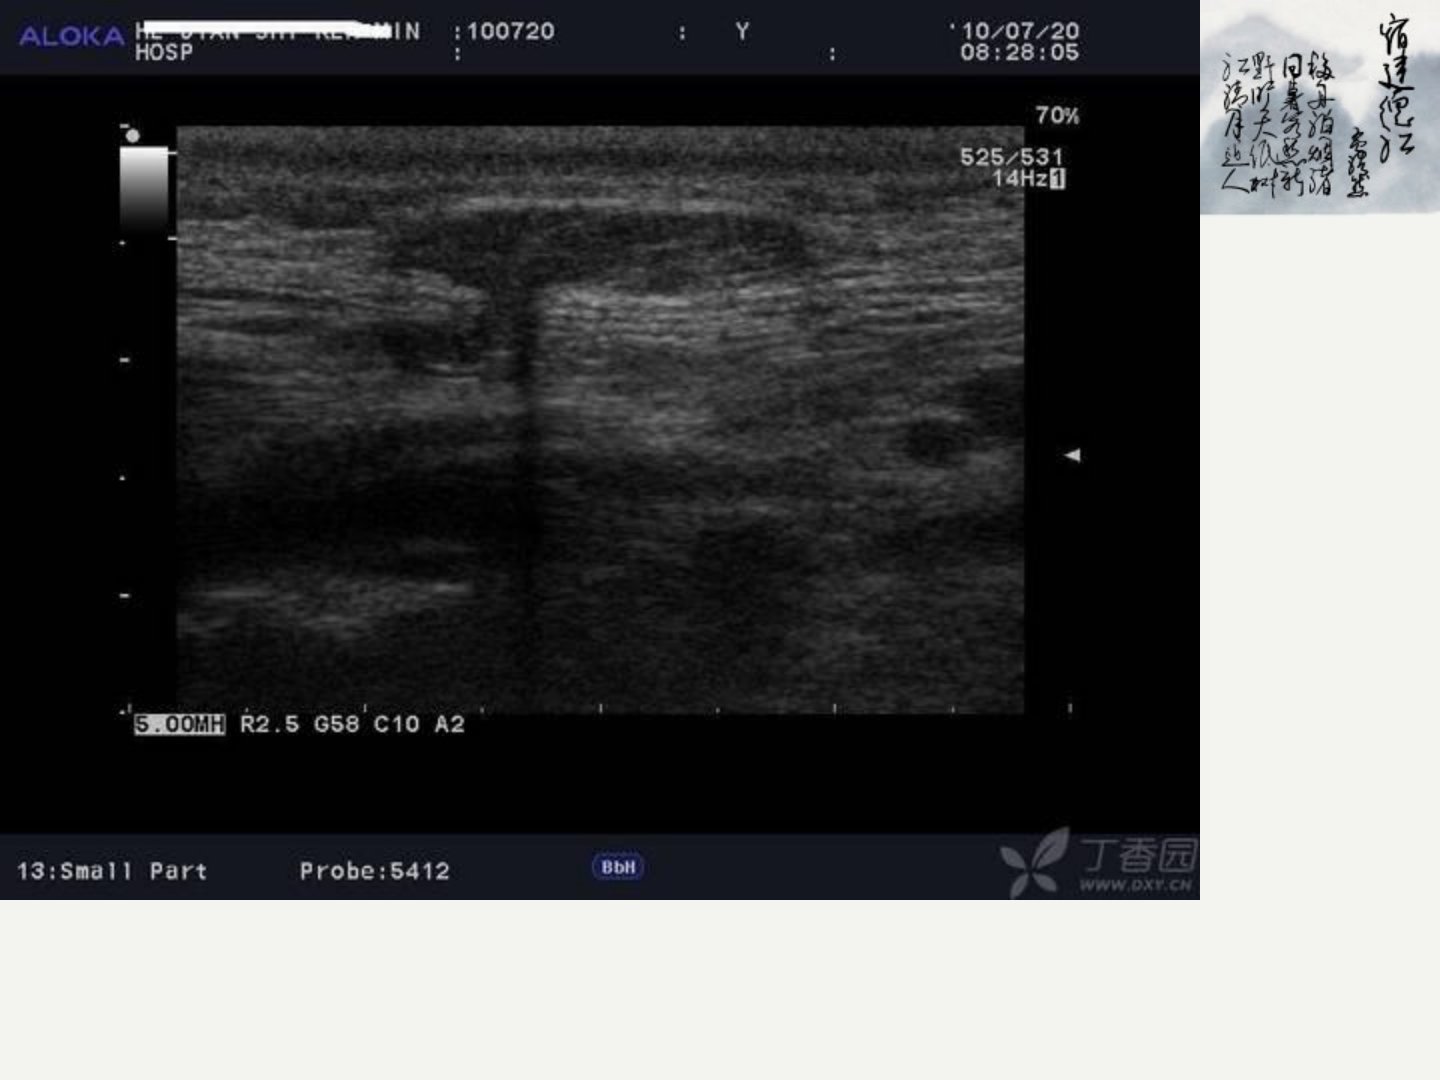

自贡市中医院功检科2013年报告聚焦胎儿腹部缺陷的超声诊断。报告首先通过病例介绍了腹白线并指出直径大于05cm、有症状、较大或有绞窄危险的白线疝需手术治疗。接着报告详细阐述了胎儿腹壁缺陷包括脐膨出和腹裂两种类型。其中脐膨出主要在孕811周形成发病率1300015000常合并先天性心脏病或肠道异常病儿不论膨出大小都应尽早手术;腹裂即胎儿真性腹壁缺损多好发于低体重儿发生率约1130000裂孔多位于腹中线右侧。两者鉴别要点在于脱出的内脏是否有包膜样结构包裹。此外报告还强调了孕中期15幅标准图观察的重要性并指出NT值测量对诊断胎儿异常有重要意义。